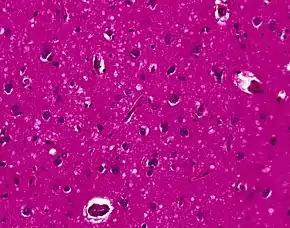

The classic histologic appearance is spongiform change in the gray matter: the presence of many round vacuoles from one to 50 micrometers in the neuropil, in all six cortical layers in the cerebral cortex or with diffuse involvement of the cerebellar molecular layer.[48] These vacuoles appear glassy or eosinophilic and may coalesce. Neuronal loss and gliosis are also seen.[49] Plaques of amyloid-like material can be seen in the neocortex in some cases of CJD.

However, extra-neuronal vacuolization can also be seen in other disease states. Diffuse cortical vacuolization occurs in Alzheimer's disease, and superficial cortical vacuolization occurs in ischemia and frontotemporal dementia. These vacuoles appear clear and punched-out. Larger vacuoles encircling neurons, vessels, and glia are a possible processing artifact.[47]

The symptoms of CJD are caused by the progressive death of the brain's nerve cells, which are associated with the build-up of abnormal prion proteins forming in the brain. When brain tissue from a person with CJD is examined under a microscope, many tiny holes can be seen where the nerve cells have died. Parts of the brain may resemble a sponge where the prion were infecting the areas of the brain.